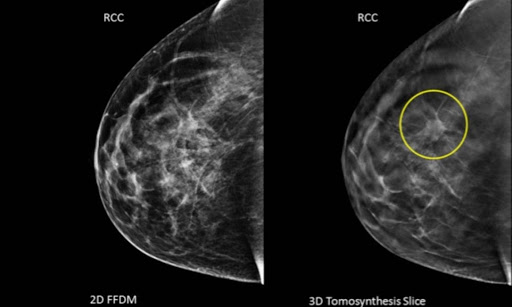

A imagem 3D (à direita) permitiu a identificação de um tumor que o exame tradicional não tinha sido capaz de identificar.

Isso traz mais segurança ao profissional que analisa as imagens, reduzindo as chances de um diagnóstico impreciso.

A tomossíntese cria imagens como se fossem finíssimas fatias da mama separadamente, evitando que essas imagens fiquem sobrepostas ou misturadas, permitindo uma definição mais minuciosa das bordas das lesões, um dos fatores de diferença entre tumores malignos e benignos.

Além disso, nos casos de lesões ainda muito pequenas, há menos chance de que elas sejam encobertas por estruturas normais.